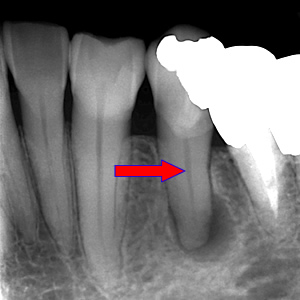

| 1.丸の中の黒く写っているところが 感染している状態です。 |

2.矢印が指しているのが根管です。 そこへお薬を詰めます。 |

3.黒い影が消え、白くなりました。 これで感染源もなくなりました。 |

CT画像を見ると根管が2本あることが分かりました。(レントゲンだけでは分かりませんでした。)

| 治療説明 | 右下第2小臼歯、他院で根管治療した後に頬側根尖部から排膿があます。X線CT画像では、根管が2本あり、そのうち舌側が根管充填されていませんでした。顕微鏡下で2根管とも根管充填処置を行い、4ヶ月で、X線透過像は消失しました。 |

|---|---|

| 治療期間 | 6〜24ヶ月 |

| 治療費用 | 150,000〜300,000円 |

| 治療に伴うリスク | 根管内からの治療で根尖病巣が治らない場合は、外科的に根尖病巣を除去する必要があります。 再根管治療を繰り返す場合、歯根の厚みが薄くなり、歯根破折のリスクが高まります。 |